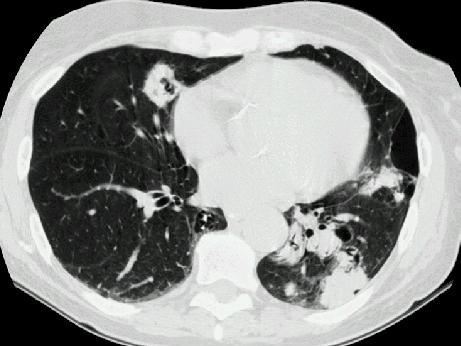

问题 多发性骨髓瘤患者出现咳嗽,咳痰,气急,胸片检查发现病变后行CT检查如图,最可能的诊断为 ( )

选项 A.肺部感染 B.两肺结核 C.骨髓瘤转移肺部 D.肺淀粉样变性 E.肺转移瘤

答案 D